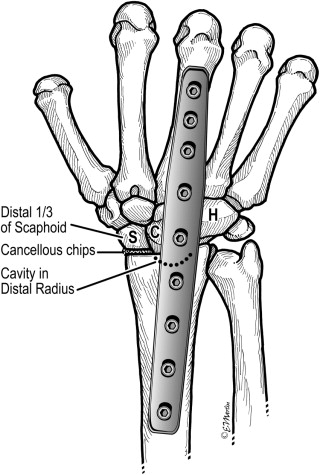

Stage III 부터는 주상골도 영향을 받기 시작하며 회전을 하거나(IIIA, cortical ring 관찰가능), carpal height 가 줄어드는 것을 확인할 수 있습니다. (IIIB), IIIA 까지는 II와 치료를 거의 동일하게 하지만, IIIB 부터는 Proximal row carpectomy 나 STT, SC fusion 등을 시행해 볼 수 있습니다.

치료 중에 IIIB 부터 시행하는 치료는 아래와 같습니다.